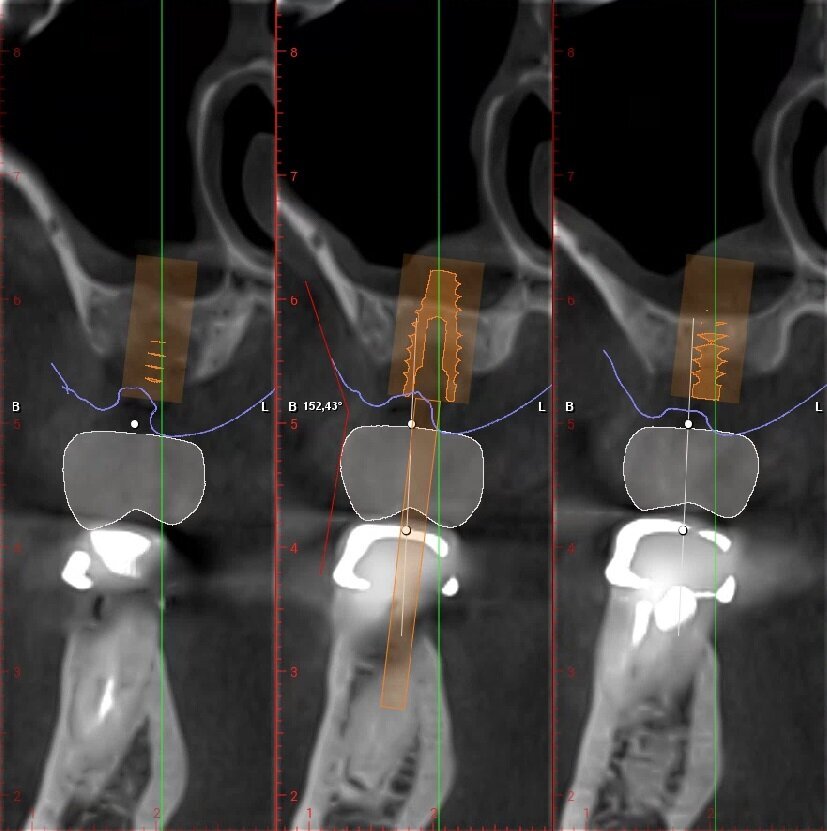

Fig. 4_Ceratura diagnostica elemento 2.5. Dimensione corono-apicale della corona congruente con elemento controlaterale 8,24 mm, tragitto trans-mucoso 3,03 mm, entità della rigenerazione ossea verticale necessaria 2,01 mm.

_Pianificazione implantare

Posizionamento protesicamente guidato dell’impianto, tenendo conto dello spessore dei tessuti molli; che idealmente dovrebbe essere intorno ai 2-3 mm. Con valori più alti di 3-4 mm è indicata una ricostruzione ossea verticale al fine di riportarne la lunghezza in un range di normalità (Figg. 6, 7).

Fig. 6_Pianificazione implantare protesicamente guidata dell’elemento 2.5.

Fig. 7_Pianificazione implantare protesicamente guidata dell’elemento 2.6.